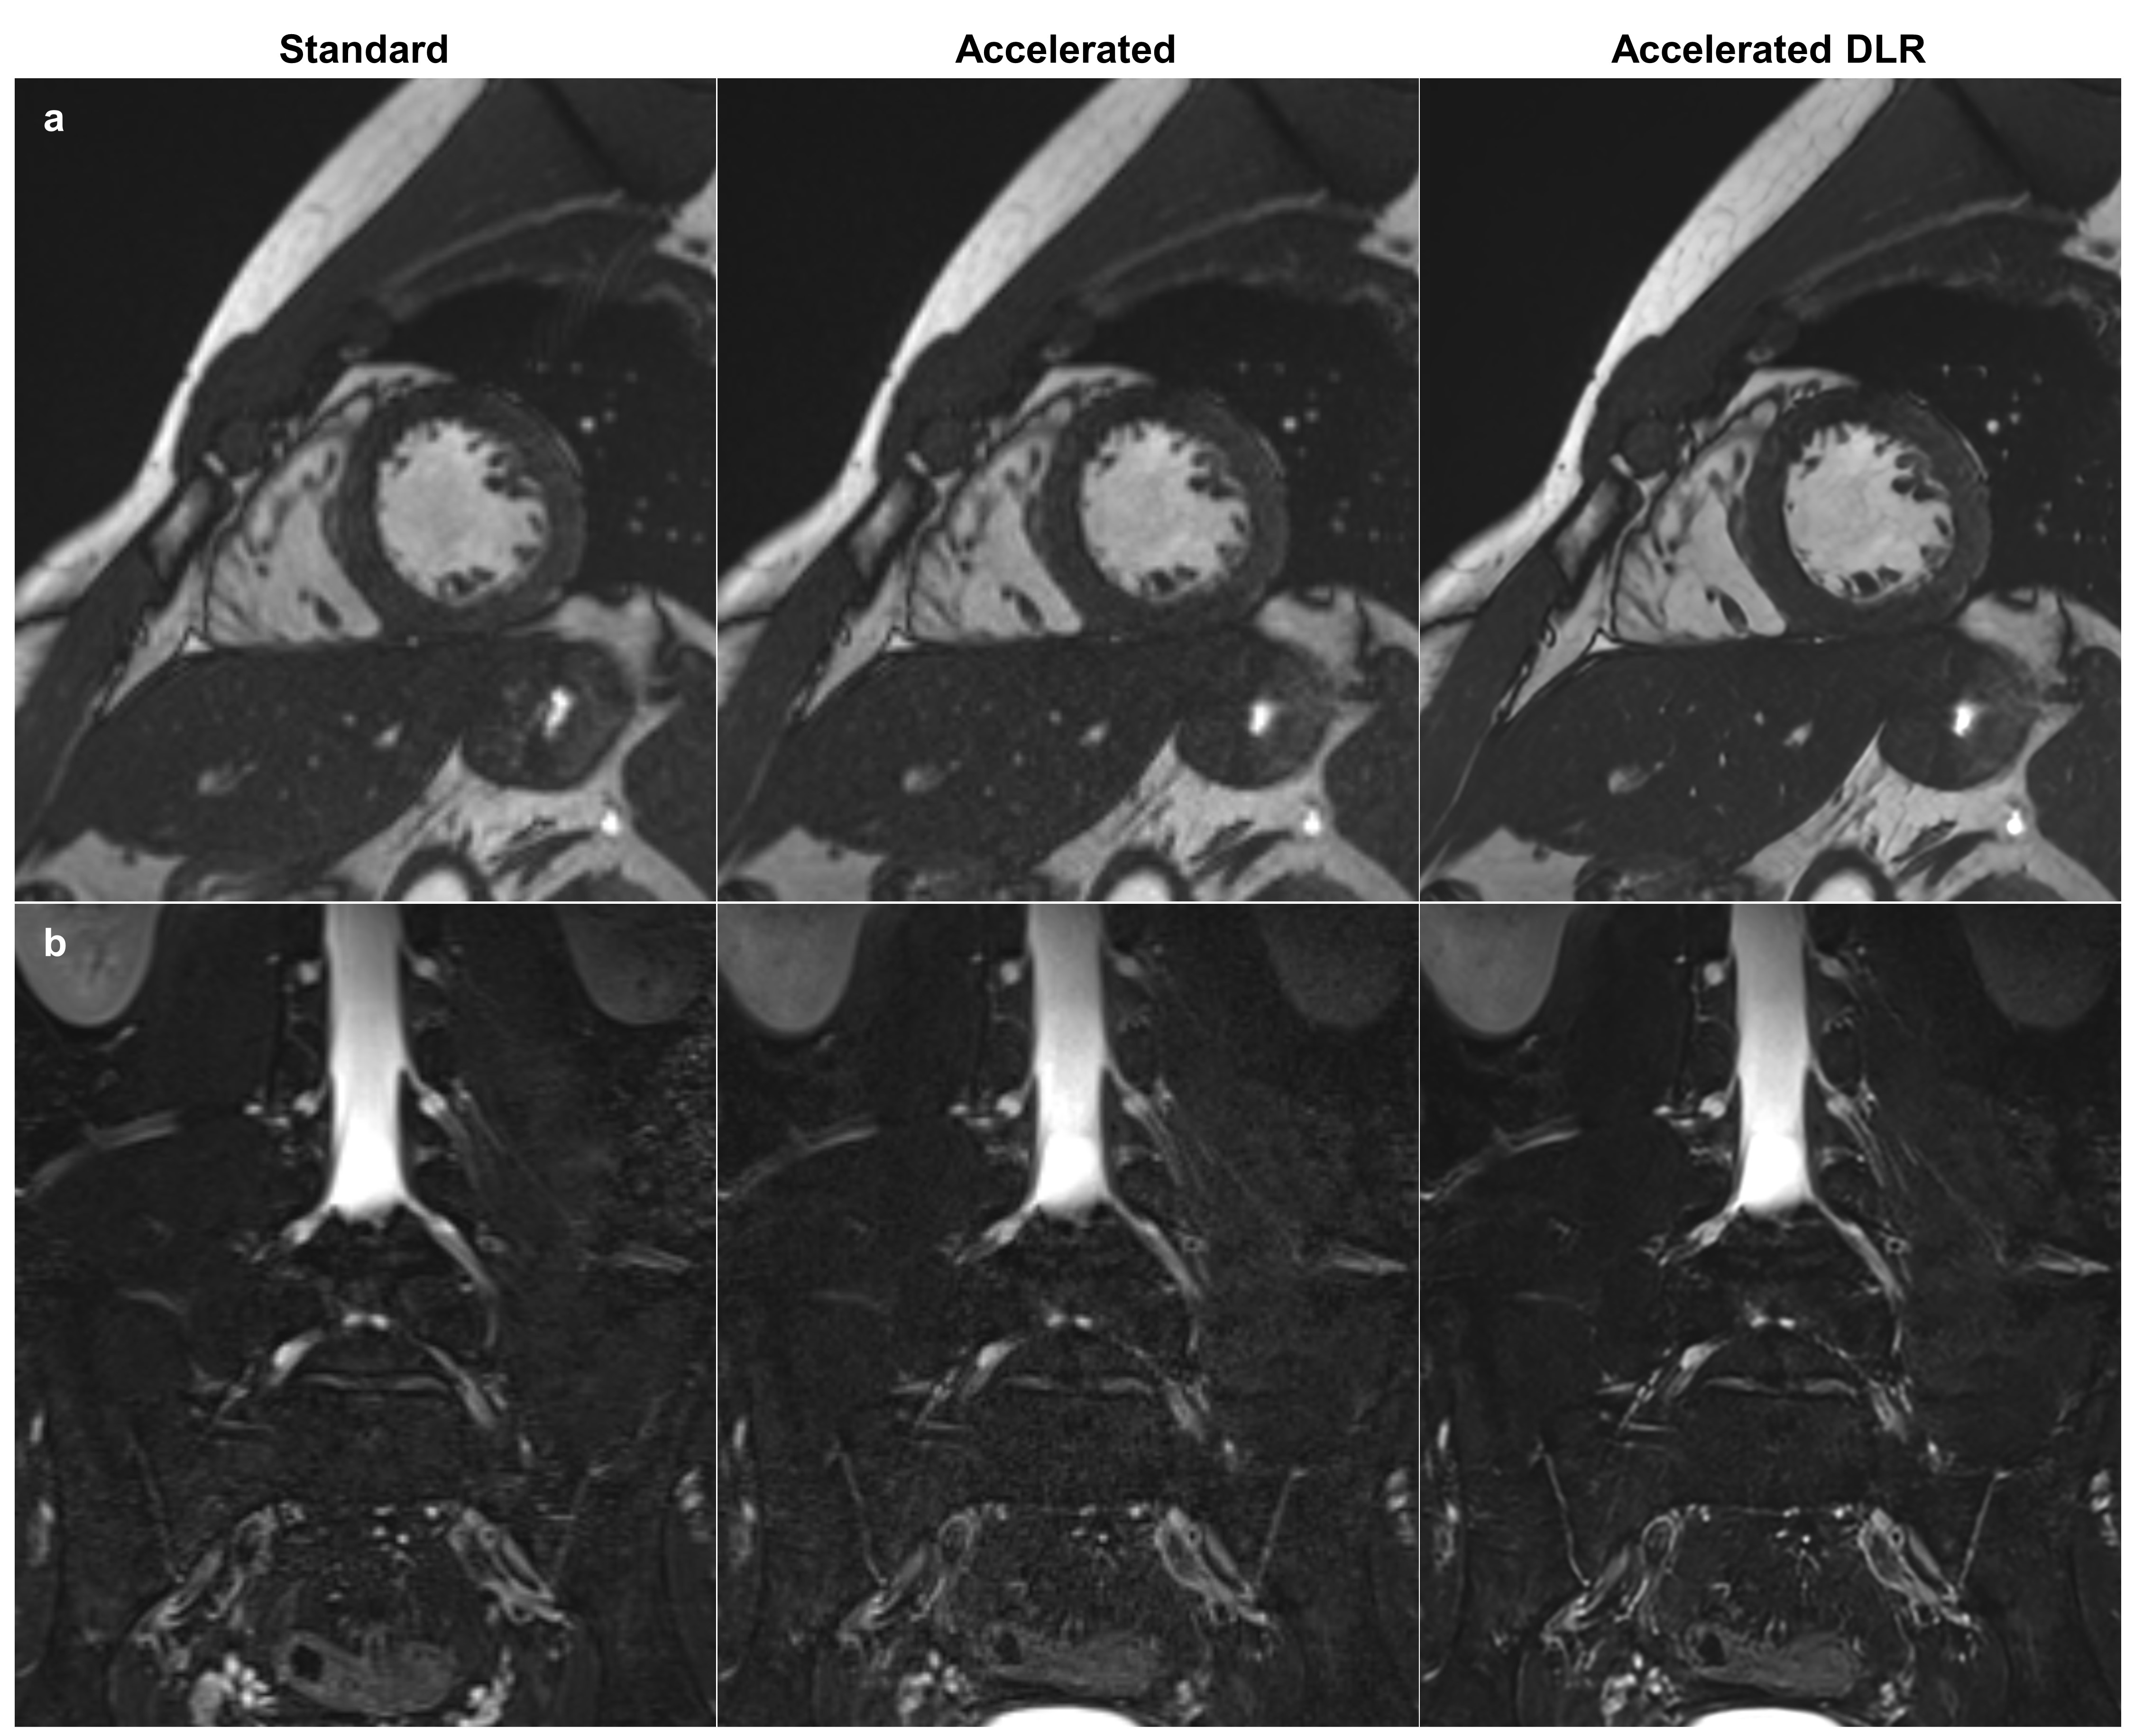

3.7 Scan time reduction across anatomical regions

To explore the model’s potential in reducing scan time, we acquired image pairs from standard and accelerated protocols across four different anatomical regions: heart, lumbosacral plexus, knee, and brain, on a 3.0T MR scanner (MAGNETOM Skyra, Siemens Healthineers) with 30-channel body coil/32-channel spine coil, a 32-channel spine coil, a 15-channel transmit/receive knee coil, and a 64-channel head/neck coil, respectively. The accelerated protocols were optimized from standard protocols to reduce scan time and increase spatial resolution, which resulted in increased noise. Table 2 summarizes the scan parameters and scan times for each protocol. After applying DLRs to the accelerated images, we visually compared them with the corresponding standard images. A noise reduction factor of 2.0 was used for the heart and knee, while a factor of 3.0 was used for the lumbosacral plexus and brain. For the knee T2WIs, a 1 mm thick multiplanar reformation (MPR) image was generated from each source image (standard, accelerated, and accelerated DLR).

Figure 9 presents standard, accelerated, and accelerated DLR images across four anatomical regions. The DLR heart cine image shows improved delineation of papillary muscles in the left ventricle. The DLR lumbosacral plexus neurography image provides clearer visualizations of nerve roots, dorsal root ganglia, and spinal nerves. The DLR knee T2WI reveals a more distinct depiction of the overall soft tissues. The DLR brain DWI exhibits superior apparent resolution, particularly in the delineation of sulci. Notably, it also demonstrates reductions in geometric distortion artifacts in the frontal lobe, attributed to the increased GRAPPA factor. In all cases, the accelerated DLR images exhibit equivalent or reduced noise levels compared to the standard images.

Refer to caption

Figure 9: Visual comparison between standard, accelerated, and accelerated DLR images across different anatomical regions. The accelerated protocols were optimized from standard protocols to reduce scan time and increase spatial resolution, which resulted in increased noise. (a) Heart cine images where each slice was acquired in a single breath-hold, with breath-hold times of 12 seconds for standard and 9 seconds for accelerated scans. (b) Lumbosacral plexus neurography images with scan times of 369 seconds for standard and 219 seconds for accelerated. (c) Reformatted knee T2-weighted images with scan times of 321 seconds for standard and 185 seconds for accelerated. (d) Brain diffusion-weighted images with scan times of 52 seconds for standard and 32 seconds for accelerated. In all cases, the accelerated DLR images exhibit boosted perceived resolution and either equivalent or reduced noise levels compared to the standard images. DLR, deep learning reconstruction.

Figure 9: Visual comparison between standard, accelerated, and accelerated DLR images across different anatomical regions (continued).